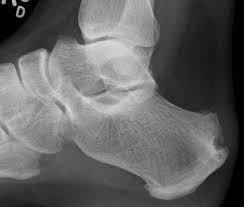

Sever's disease represents inflammation of the heel bone apophyse, and is most often the result of excessive load during intense physical activity. It is common in young athletes aged 8 to 12 years. The pain most often occurs in the heel during or after activity, and may intensify the next day.